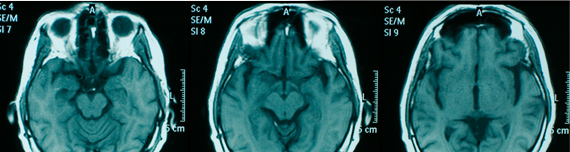

Contrast Imaging 'agents' are used to get more clinical information for diagnosis, staging therapy and treatment from images. With technological advances in imaging modalities and Nuclear Medicine, imaging is now possible at the molecular level providing deep insight into progression of disease and efficacy of drugs. We are recognized as the leading CRO in this specialized area.

“Marketing approval by US FDA & EMA of Piramal Imaging’s ‘NeuraCeq’ for PET Imaging of Neuritic Beta-Amyloid Plaques, in the Brain of patients being evaluated for Alzheimer’s disease” Approval was based on an intercontinental study of patients with a high probability of beta-amyloid deposition where the primary end point was pathology of the brain donated after death. In this highly challenging study, sites in Australia, Japan and Europe were audited by EMA and FDA for GCP compliance.

Marketing approval was granted by the US FDA for a gadolinium contrast agent in breast MR imaging, the first contrast agent approved for this indication in the US.

Contrast imaging agent clinical trials expert- We have contributed to the development of several contrast agents. Phase Zero study using micro dosing, First in Man study, early stage studies, to large intercontinental Ph III pivotal studies have been conducted by us.

We have successfully completed as CRO the largest number of contrast agent studies. We have enrolled nearly 6000 patients in these studies in five continents. We have experience in complex paediatric imaging studies. |